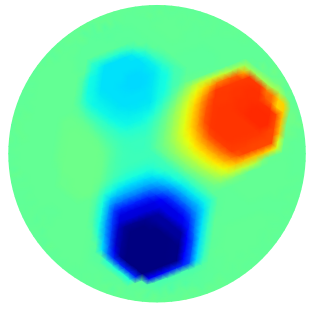

| GT | PGM-TV- | PGM-TV | PGM-- | PGM- | |

|---|---|---|---|---|---|

|

|

|

|

|

|

| FN=0.0 % | PSNR=32.84 | PSNR=28.78 | PSNR=27.19 | PSNR=22.04 | |

|

|

|

|

|

|

| FN=0.24% | PSNR=24.555 | PSNR=23.1313 | PSNR=23.1387 | PSNR=20.051 | |

|

|

|

|

|

|

| FN=0.0% | PSNR=27.53 | PSNR=25.99 | PSNR=26.93 | PSNR=22.74 |

In order to investigate the influence on the performance of the Oracle-Net in the EIT reconstruction problem (10), we compared the results of PGM-TV- and PGM--, which exploit the Oracle-Net estimated support, with the standard PGM algorithms PGM-TV and PGM- analogously regularized. In all the reported experiments, we selected the optimal value through trials and errors, while the value was set to

First, we consider the case where the measurement error in (1) vanishes.

In Fig.4 we show some sample conductivity reconstructions and we report below the corresponding PSNR evaluation. For each sample, the first column represents the estimated support pre-computed by the Oracle-Net together with the FN value associated, the second column illustrates the target ground truth (GT) reconstruction, and from the third to the sixth columns the computed reconstructions are shown for the different algorithms together with the PSNR values obtained. From a visual inspection of the illustrated results and from the PSNR values reported, we can observe the benefit of incorporating the Oracle-Net estimated support into the PGM algorithmic framework. PGM-TV and PGM- achieve lower performance than their Oracle-Net-based counterparts. Moreover, the use of the TV regularizer seems to be beneficial with or without Oracle exploitation.